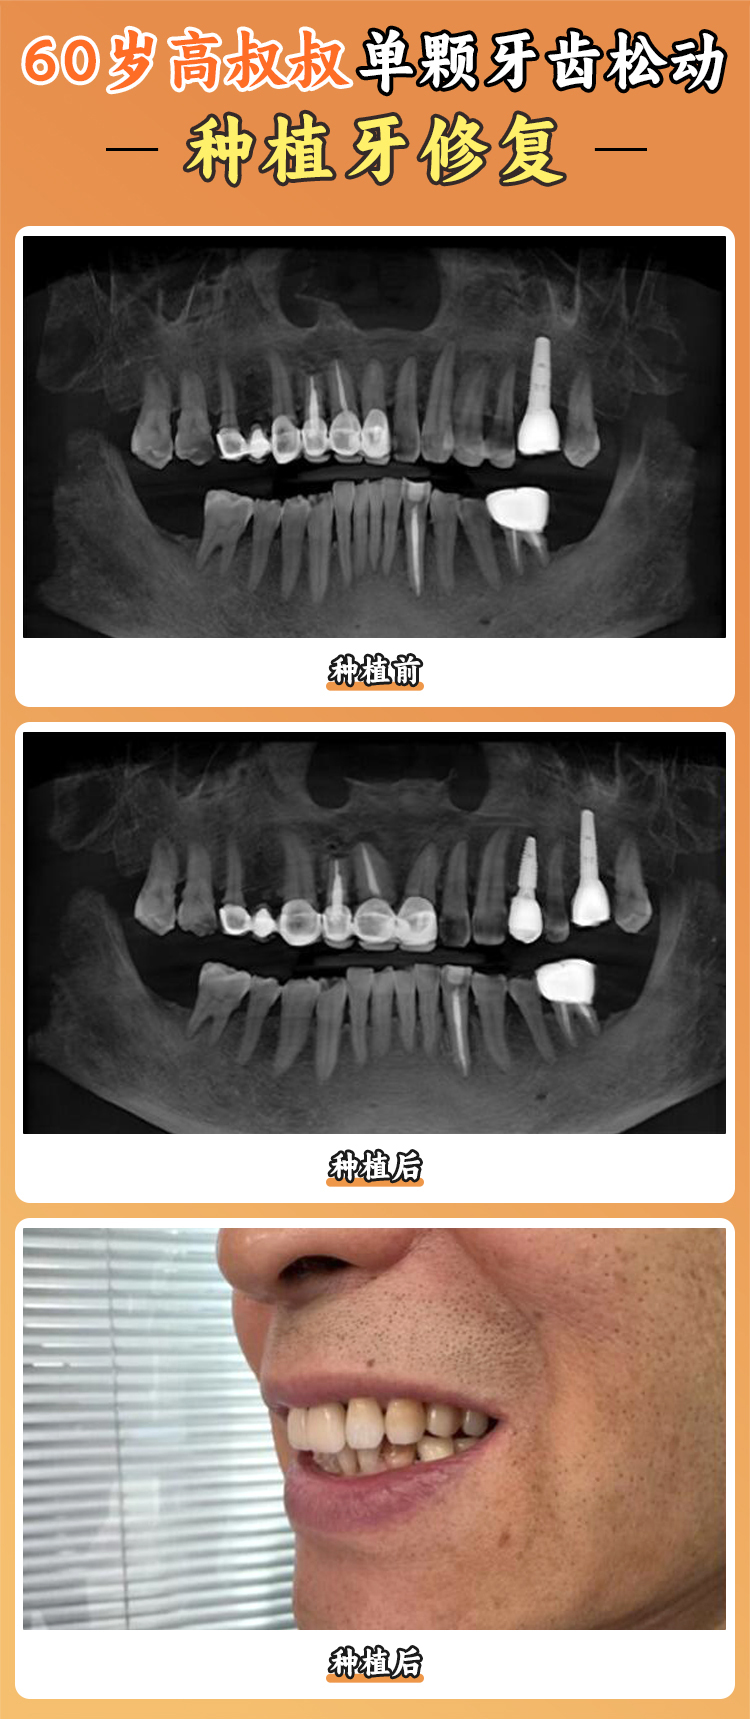

1. 初診檢查:拍攝全景片或CBCT,了解牙槽骨情況。

2. 種植設計:醫(yī)生根據(jù)影像資料制定個性化種植方案。